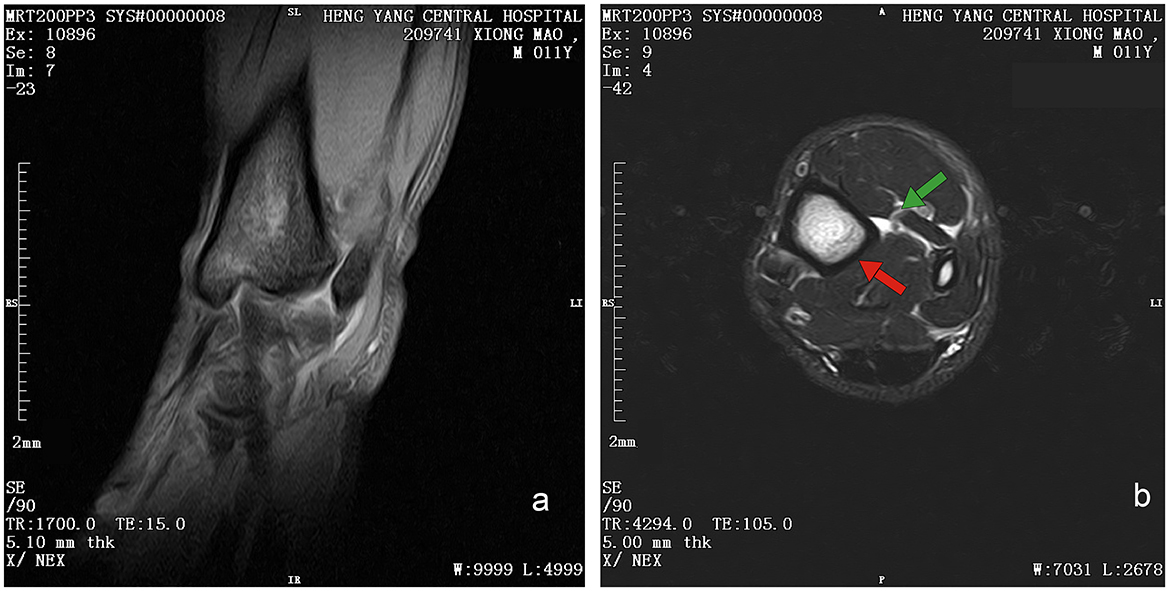

Initial clinical evaluation involved observation and palpation of the limbs, followed by blood collection for routine hematological and biochemical testing. A non-anesthetic examination revealed mild atrophy of the left hind limb, with no pain response on palpation. There was mild alopecia on the medial aspect of the left hind limb's thigh and increased skin temperature, without detected swelling, trauma, or joint deformity. Additionally, claw abrasion was noted on the right paw, accompanied by erythema and swelling of the right paw pad (Figure 1b). No other abnormalities were detected during this initial assessment. Blood samples were collected concurrently for routine blood and biochemical tests, which subsequently revealed low lymphocyte and platelet counts, and the levels of total cholesterol (TC) and triglycerides (TG) were elevated. However, no significant increase in C-reactive protein (CRP) was observed (since there was no reference range for CRP in giant pandas, human levels were used here; Table 1). Throughout this examination phase, the panda's diet and weight remained stable, consistent with its baseline status. 3 days later, under general anesthesia, further examination was performed. The panda's body temperature was normal, and no external injuries, or draining fistulas were observed. Subsequently, advanced imaging modalities were employed. Non-enhanced scanning of both hind limbs was performed using a Toshiba Activion 16 multislice CT scanner (TOSHIBA, Tokyo, Japan). The panda was placed in a dorsal recumbency. The scanning protocol included both hindlimbs, extending from the femur to the phalanges. A helical scan mode was used with a gantry rotation time of 0.5 s per rotation and a detector configuration of 16 rows × 1.0 mm. The beam collimation width was matched to the detector configuration (16 × 1.0 mm), with an original slice thickness of 1.0 mm. Tube voltage was set at 120 kV and tube current at 70 mA. The pitch was 1.375:1. The scan field of view (SFOV) was adjusted according to the number of hind limbs: 450 mm for bilateral and 400 mm for unilateral examinations. The Z-axis scanning range was ~600 mm, and the original slice thickness was fixed at 1.0 mm. Image reconstruction parameters were tailored to diagnostic needs. For bone evaluation, images were reconstructed with a slice thickness of 5.0 mm. For soft tissue evaluation, images were reconstructed with a slice thickness of 1.1 mm and a reconstruction interval of 0.69 mm. A high-resolution bone algorithm (Bone 5.0) was applied for bone reconstruction, and a standard soft tissue algorithm (Soft Tissue 1.1) was applied for soft tissue reconstruction. The reconstruction matrix was uniformly 512 × 512, with a pixel size of 0.8 mm. The display field of view (DFOV) was set to 350 mm. For the bone window, window width and level were 2,000 HU and 500 HU, respectively; for the soft tissue window, window width and level were 1,876 HU was 492 HU, respectively. CT scans revealed no evidence of fractures, joint space narrowing or widening, osteophyte formation, or other bony abnormalities in either hind limb (Figure 2). With the permission of the government, these CT scans were read jointly by radiologists and veterinarians, who confirmed that there were no osseous abnormalities in the two hind limbs. Following the CT examination, a Toshiba Vantage Titan 1.5T MRI (TOSHIBA, Tokyo, Japan) was used to perform MRI examinations. Image acquisition is carried out with a slice thickness of 3–5 mm and an interval of 1–2 mm. First, conventional SE sequences were used for image acquisition (T1W: TR 1,700 ms, TE 15 ms); T2W: TR 4,294 ms, TE 105 ms). T1W sagittal images of the tarsus show that the bony structures, including the distal tibia, talus, and calcaneus, have distinct and well-defined margins. The bone marrow signal within these bones is homogeneous, with no apparent abnormal hypointense or hyperintense areas detected. The articular cartilage of the tarsus maintains a smooth surface, and its signal intensity on T1W imaging is consistent with that of normal articular cartilage, appearing isointense relative to the adjacent muscle tissue in most regions. The tarsus ligaments, such as the dorsal talofibular ligament and calcaneofibular ligament (visualized in appropriate sections), exhibit normal low–signal characteristics on T1W sequences, without evidence of discontinuity, thickening, or abnormal signal intensity. The surrounding soft tissues, including the tendons (e.g., the Achilles tendon, tibialis cranial) and the joint capsule, display a normal layered structure, with no significant swelling, thickening, or abnormal signal intensity changes. The T2W transverse image shows that patchy high signals are found in the soft tissues around the distal tibia and the plantar aspect of the tarsus calcaneus, with indistinct edges. The signal intensity is higher than that of the adjacent normal muscle tissue. The high intensity around the distal tibia is mainly located in the interosseous space or interosseous muscle on the inner side of the distal tibia. The high signal plantar calcaneus is mainly distributed around the subcutaneous soft tissue on the inner, outer and plantar sides of the Achilles tendon (Figure 3). At the same time, there are also some high signal intensities in soft tissues of the plantar aspect of tarsus. Based on MRI findings, a diagnosis of osteomyelitis in the left hindlimb was made.

Figure 3. Magnetic resonance image of left hind limb of giant panda. (a) T1W sequence of sagittal plane. Sequence Parameters: repeat time (TR) of 1,700 ms, echo time (TE) 15 ms, slice thickness of 3.8 mm, window width (W) of 6,438 HU, and window level (L) of 3,192 HU. Bony structures (distal tibia, talus, calcaneus) show clear margins with homogeneous bone marrow signal (isointense to muscle on T1W). Articular cartilage appears smooth with isointense signal; No definite bony cortex disruption or abnormal signal involvement of bones. (b) T2W sequence of transverse plane. Sequence Parameters: repeat time (TR) of 4,294 ms, echo time (TE) 105 ms, slice thickness of 5 mm, window width (W) of 7,031 HU, and window level (L) of 2,678 HU. Patchy hyperintensities (long T2 signal, suggestive of edema/inflammation) are noted in soft tissues around the distal tibia (intermuscular space); Focal hyperintensities are observed in soft tissues posterior to the calcaneus (around the Achilles tendon), with clear demarcation from the tendon.

CT provides high density resolution, enabling clear detection of bone damage, particularly cortical bone destruction Early subperiosteal abscess formation can be identified by quantitative analysis of lesion attenuation values (28). However, conventional CT, as used in the present study, has limited sensitivity for detecting early marrow involvement in osteomyelitis. In its early stages, osteomyelitis may lack characteristic findings such as lysis, soft tissues changes, or clear inflammatory infiltration, making accurate localization and assessment of lesion extent challenging (29). Notably, dual-energy CT—an advanced modality capable of detecting bone edema—was not available for this study. Although quantitative analysis of CT attenuation values may improve detection of early lesions, this was not performed in the present cases. Consistent with the limitations of conventional CT in identifying subtle early changes, CT findings were normal, prompting additional MRI examination to clarify the condition. MRI, provides higher soft tissue resolution and contrast, excelling in detecting early marrow changes, making it a preferred for early diagnosis of osteomyelitis (30). The MRI results of the giant panda's lower limb showed isointense signals on T1WI, indicating normal bone morphology, which was consistent with the CT findings. However, the high signal on T2WI indicated the presence of a lesions. Given that this giant panda had no recent history of trauma, and its MRI scans revealed no trauma-specific imaging features—such as fracture lines, acute bone marrow contusions with diffuse hemorrhagic signals, or signs of soft tissue laceration—these findings effectively ruled out traumatic abnormalities in bone marrow signals. Similarly, no masses were noted on imaging, suggesting the absence of neoplastic lesions. Thus, the combined use of CT and MRI in this giant panda case highlights their complementary roles in diagnosing bone and soft tissue abnormalities. While CT effectively rules out gross bony lesions, MRI's superior sensitivity to early marrow changes and soft tissue pathology enables the detection of subtle lesions that may indicate early-stage osteomyelitis.